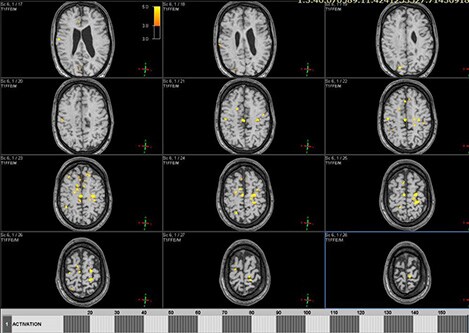

Цель: Апробация и внедрение в клиническую практику современных методик фМРТ и DTI для оценки структурных и функциональных изменений при нарушениях движения у детей. Описание проекта: Для Детского Церебрального Паралича характерно наличие незначительных структурных повреждений [1], при этом неясна их связь с нарушениями двигательных функций. фМРТ позволяет выявить зоны активации мозга при выполнении движений и оценить сложность выполнения задания по объему зон активации (Рис 1). МР-трактография позволяет исследовать структуру и диффузионные характеристики проводящих путей мозга (Рис 2). МР-волюметрия также позволяет оценить объем основных структур мозга и выявить аномалии развития, кортикальные дисплазии и патологии белого вещества мозга (Рис 3.). Результаты: Проведена клиническая апробация предложенных методик. Результаты представлены на медицинских неврологических конгрессах.

Рис. 3. МРТ данные пациента с ДЦП: на FLAIR изображениях структурные изменения минимальны.